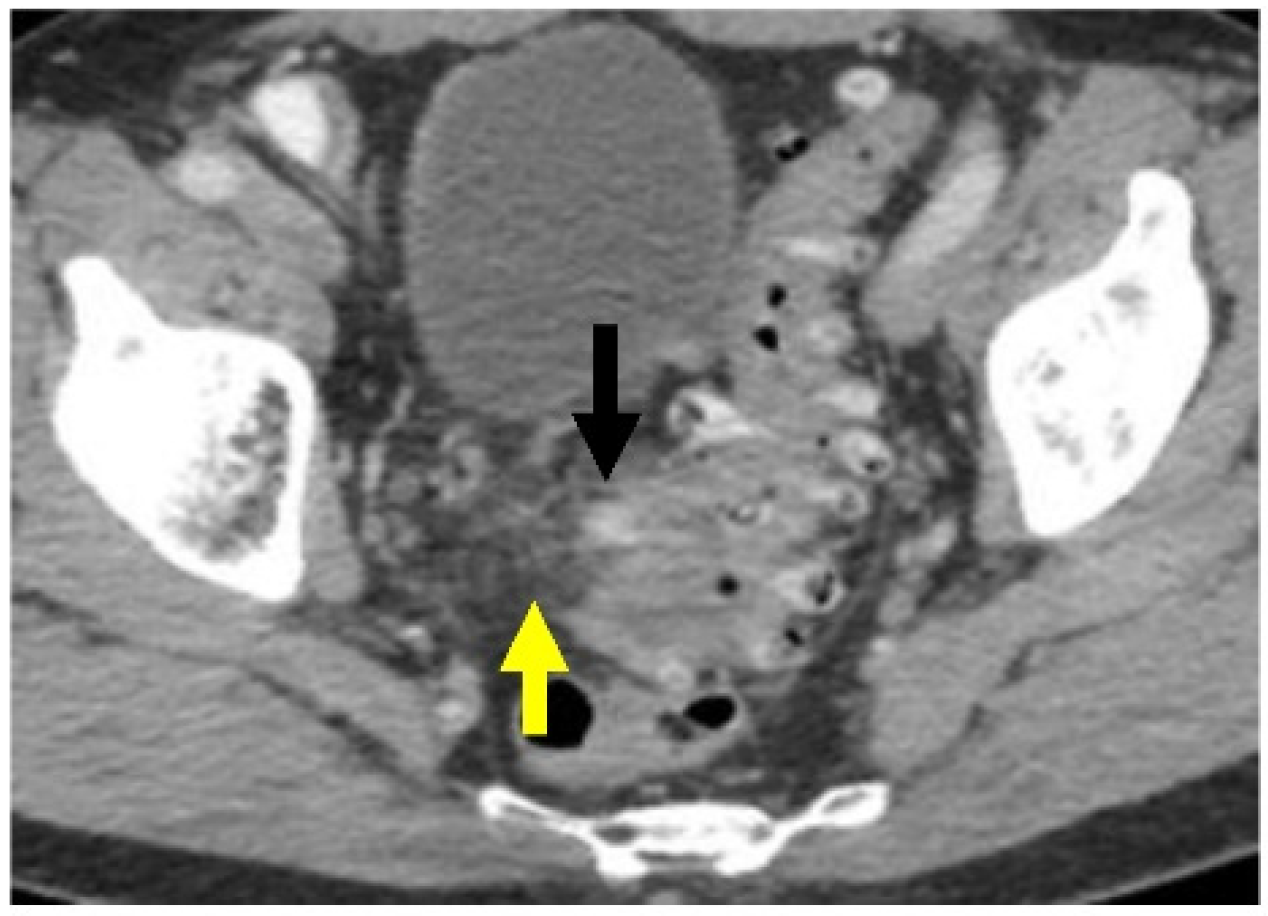

Figure 5.

Acute sigmoid diverticulitis complicated by peridiverticular abscess. Axial CT with IV contrast through the pelvis. There is a rim-enhancing collection of fluid and air along the medial wall of the sigmoid colon (yellow arrow), compatible with abscess. This also abuts the appendix (black arrow), with possible fistulous communication.

CT scanning can show complicated disease as a peridiverticular mesenteric inflammatory reaction (Hinchey Ib) or microperforation with adjacent extraluminal air (Figure 6). Contrast is also helpful to evaluate for potential abscess (Hinchey Ia or II), where rim-enhancement will be seen (Figure 5).